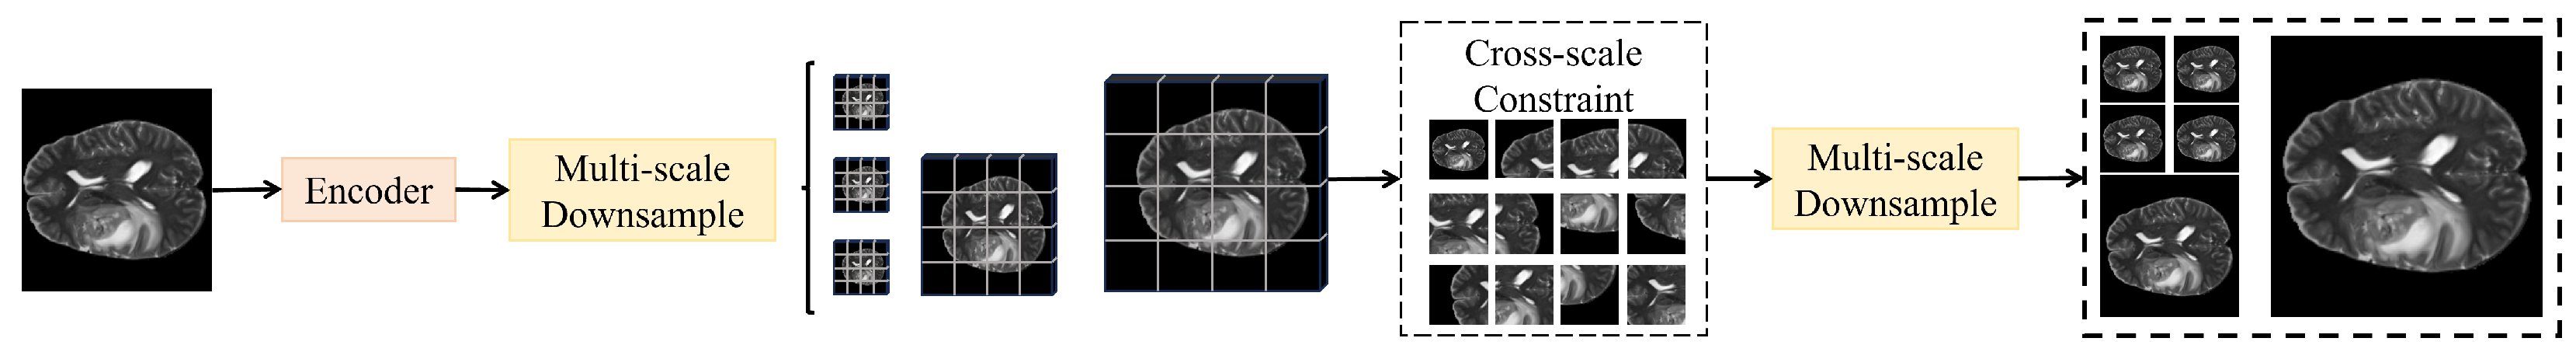

3.3.1. Overall

The overall method is built upon a unified dual-branch architecture with a shared encoder–decoder backbone. The processed medical image x is first fed into a shared encoder E, which is implemented as a hybrid U-Net–Transformer structure consisting of convolutional stem layers followed by hierarchical transformer blocks. The encoder extracts multi-scale features through progressive down-sampling, where spatial resolution gradually decreases while semantic abstraction increases. The parameters of E are fully shared between the two downstream branches to ensure semantic consistency and parameter efficiency. Both branches thus operate on identical feature maps produced by the same encoder weights. To facilitate faster convergence and stable representation learning, E is initialized with ImageNet-pretrained weights and then fine-tuned on medical imaging data. The high-resolution layers and are directed to the local detail attention branch, which focuses on fine-grained contour and texture modeling. This branch employs channel–spatial joint gating and boundary-sensitive residual units to assign normalized attention weights within to regions containing potential boundaries or microstructures, yielding enhanced local representations . A texture–edge embedding unit further preserves structural granularity and mitigates noise, while lightweight depthwise separable convolutions and pointwise re-calibration stabilize responses for small-scale lesions. The deeper layers and are processed by the global context attention branch, which constructs query, key, and value tensors for self-attention aggregation. Relationships are first captured within non-overlapping local windows and subsequently extended across windows via shifted-window interaction, enabling long-range dependency modeling and the generation of globally enriched features containing organ topology and lesion-level semantics. Relative position encoding is incorporated to maintain spatial consistency and reduce boundary mismatches. While the two branches operate independently in their respective resolution spaces, feature interaction is implicitly maintained through the shared encoder and explicitly reinforced during the fusion stage. At the fusion stage, and are projected to a unified embedding dimension by a dynamic cross-scale fusion module and combined through pixel-wise adaptive weighting and concatenation to yield the fused representation Z. The decoder adopts a U-shaped progressive up-sampling strategy, aligning Z with encoder features via skip connections to produce multi-scale predictions . A cross-scale consistency constraint enforces bidirectional alignment among predictions, stabilizing outputs across scales. The overall loss integrates region-overlap and boundary-similarity terms for joint optimization. A global pooling operation applied to Z, followed by a lightweight classification head, generates lesion class probabilities, enabling joint segmentation and recognition within a unified backbone. During inference, the model outputs multi-scale masks and classification scores from coarse to fine, refined via an adaptive ensemble guided by scale reliability and uncertainty estimation. Residual connections, layer normalization, and attention temperature scaling ensure numerical stability, while separable convolutions and sparse attention mechanisms effectively control computational cost, forming an integrated “encoding–dual-branch attention–dynamic fusion–consistency constraint–multi-head output” framework for lesion segmentation and recognition. To facilitate understanding of the computational flow and feature resolutions, Table 2 summarizes the main operations and tensor dimensions across the proposed framework.

3.3.4. Cross-Scale Consistency Constraint Module

The cross-scale consistency constraint module is designed to address the inconsistency problem among predictions at different scales, ensuring that segmentation results maintain semantic and boundary coherence across multi-level outputs. As shown in Figure 4, this module operates directly on the multi-scale predictions generated by the decoder, where , , , , and denotes the binary segmentation mask channels.

Figure 4.

Illustration of the cross-scale consistency constraint module.

The core idea of the module is to establish coordination between local and global predictions across scales through bidirectional mapping and consistency constraints. Specifically, a convolution is first applied to project each scale prediction into a unified embedding dimension , followed by upsampling and downsampling operations that align all predictions to an intermediate resolution of , forming the aligned set . At this scale, the cross-scale consistency loss is introduced: